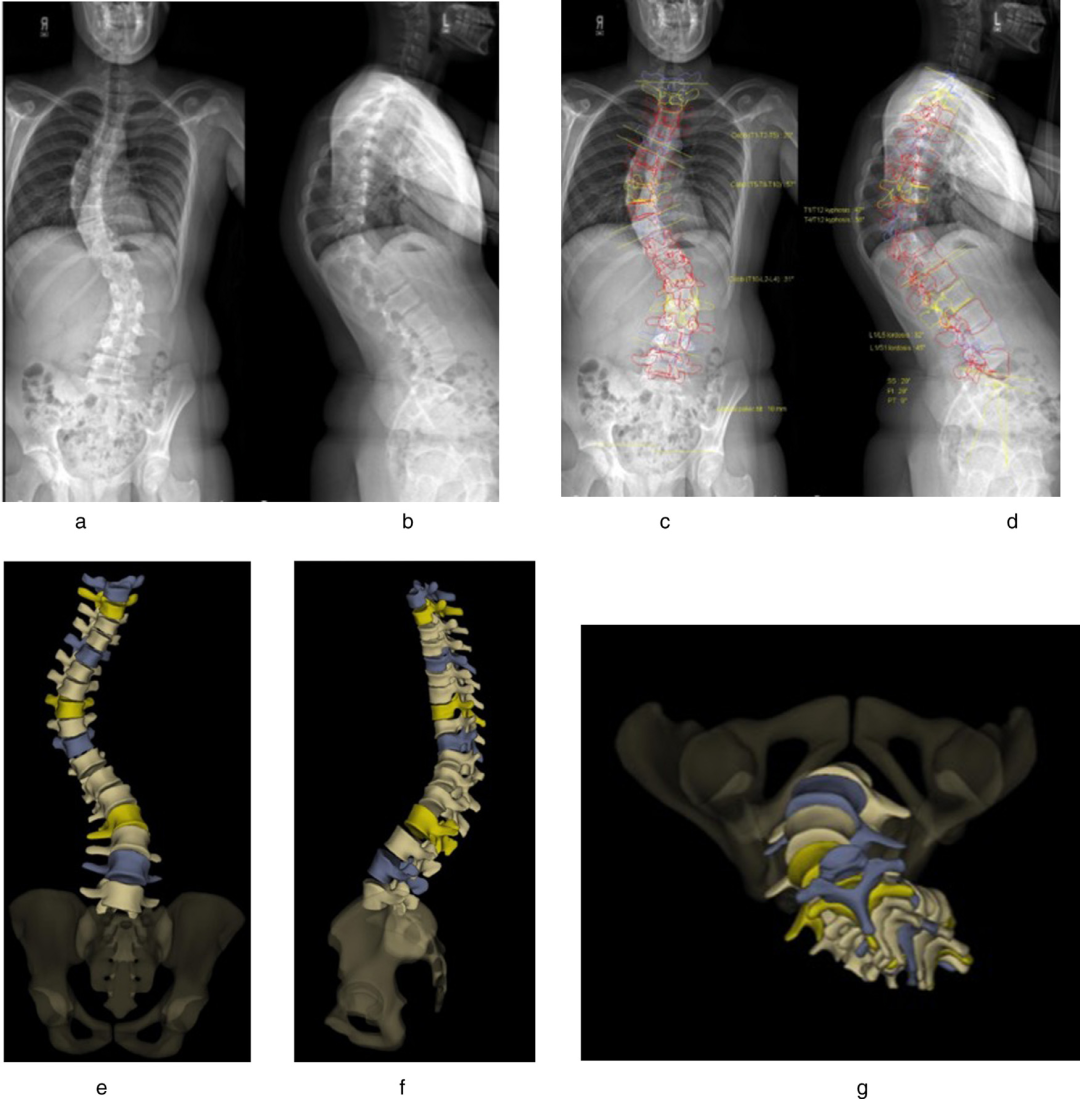

(一)脊柱側(cè)彎

脊柱側(cè)彎是一種三維脊柱畸形,涉及冠狀面的側(cè)向彎曲、矢狀面的后凸或前凸以及水平面的椎體旋轉(zhuǎn)。EOS 成像能夠在患者站立負重狀態(tài)下準確評估脊柱的真正彎曲程度和椎體形態(tài),這對于先天性脊柱側(cè)彎、神經(jīng)肌肉型脊柱側(cè)彎和特發(fā)性脊柱側(cè)彎的診斷和治療決策至關(guān)重要。通過三維重建,醫(yī)生可以清晰地觀察到脊柱的三維結(jié)構(gòu),為制定個性化的治療方案提供依據(jù),如保守觀察、支具治療或手術(shù)固定。

脊柱側(cè)彎EOS成像

(二)三維成像能力

EOS 的雙平面成像能夠生成脊柱和下肢的三維表面重建圖像,為醫(yī)生提供了更為直觀和全面的解剖信息。這種三維重建對于準確評估脊柱的旋轉(zhuǎn)程度、復雜脊柱畸形以及下肢骨骼的扭轉(zhuǎn)異常等具有重要意義,有助于制定更為精準的治療計劃。